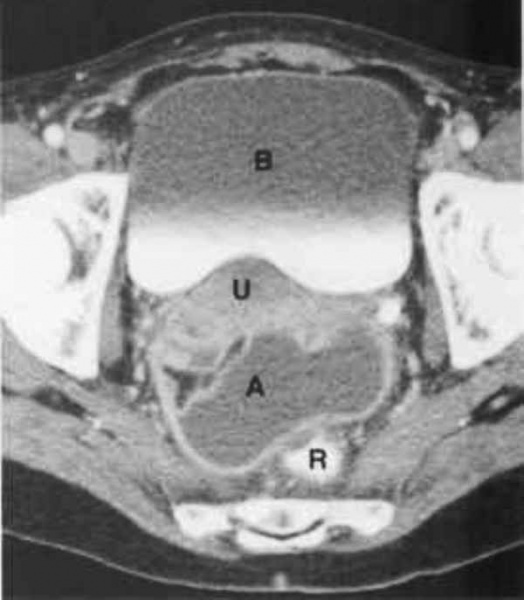

КТ органов малого таза. На снимке: абсцесс, отграниченный стенкой (А), прямая кишка (R), матка (U), мочевой пузырь (B)

Для дифференциальной диагностики с тубоовариальным абсцессом у женщин проводится УЗИ малого таза; для исключения абсцесса предстательной железы у мужчин – УЗИ простаты.

В сложно дифференцируемых случаях может потребоваться выполнение компьютерной томографии, МРТ. Для окончательного распознавания абсцесса дугласова пространства прибегают к диагностической пункции гнойника под ультразвуковым наведением через прямую кишку либо задний свод влагалища. Полученное гнойное содержимое подвергается бактериологическому исследованию.